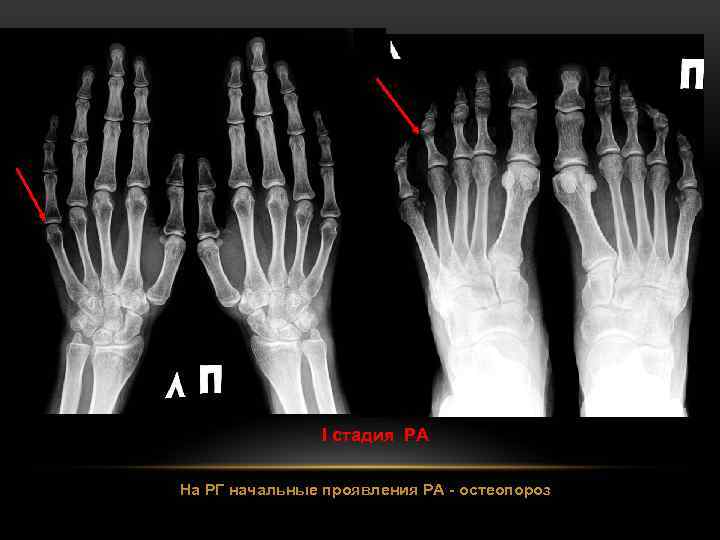

РЕВМАТОИДНЫЙ АРТРИТ Суставный синдром - ведущее клиническое проявление ревматоидного артрита (РА). Рентгенологически выделяют 4 стадии РА: I стадия (начальная) - околосуставной остеопороз; II стадия - остеопороз + сужение суставной щели; III стадия – остеопороз + сужение суставной щели + эрозии суставных поверхностей; IV стадия - сочетание признаков III стадии и анкилоза сустава. Раньше всего рентгенологические изменения при РА появляются в суставах кистей и плюснефаланговых суставах. “Ревматоидпая кисть”

I стадия РА На РГ начальные проявления РА - остеопороз